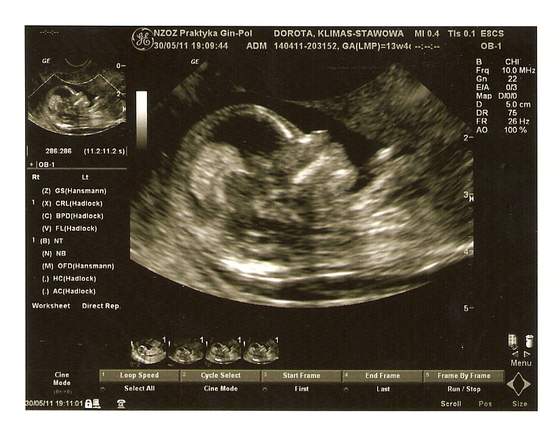

wiec tak moje drogie byłam u lekarza badania prenatalne wyszły dobrze więc nie mam czym się martwić -czego życzę wszystkim przyszłym mamusią wizyta trwała troszkę dłużej niż zwykle bo oglądałam moją kluskę co wyprawia w brzuszku

mój maluszek mierzy 7,10 cm więc miałam już na co popatrzeć :-)przeżyłam ta wizytę jak bym pierwszy raz na USG była

oczywiście zdjęcia też musiałam mieć więc podzielę się z wami moim szczęściem

zadarty nosek

no i te Ustka normalnie aż mi łezki u gina poleciały ..